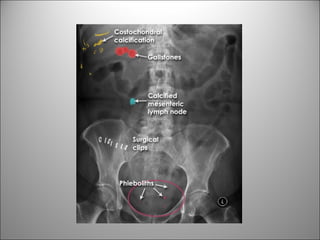

CALCIFICACIONES Y ARTEFACTOS

PATOLOGÍA FRECUENTE

LITIASIS

MIOMAS

LITIASIS BILIAR

CALCIFICACIONES AORTICAS